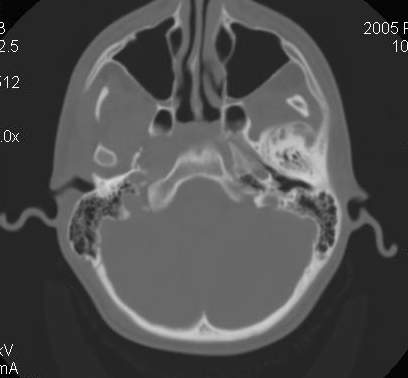

Пациент В., 13 лет. Диагноз: Костный анкилоз левого височно-нижнечелюстного сустава (ВНЧС), левосторонняя микрогения. Болеет с 2-х летнего возраста. Возможная причина развития анкилоза – воспалительный процесс (в первые 1,5 года жизни часто болел простудными заболеваниями, травму родители отрицают). В 3 и 5 лет проводилась редрессация – безуспешно.Прилагаются: ортопантомограмма, кадры СКТ с 3Д реконструкцией. Вопросы: определение тактики лечения – вид и сроки реконструктивно-пластической операции (этапов операции), а именно – неоартропластики и устранения микрогении, медикаментозная терапия в до- и послеоперационный период, ортодонтическое лечение.